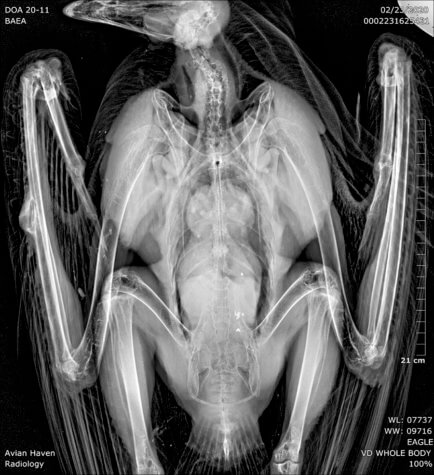

ITHACA, N.Y. — The comeback of bald eagles may be in danger, not from hunters, but from the ammunition hunters use to kill other animals. Researchers from Cornell University report that the bald eagle’s resurgence is at risk due to lead poisoning from bullet fragments in the majestic bird’s food.

Now, the new study reveals lead poisoning caused by the consumption of dead animal carcasses left behind by hunters has reduced the population growth among American bald eagles by four to six percent annually in the Northeast.

Many hunters tend to “field dress” deer killed with lead ammunition, leaving behind contaminated organs. Eventually, bald eagles come along to eat and scavenge those leftover carcasses. It’s important to note, however, eagles aren’t the only animals consuming lead-filled animal remains. Trail cameras confirm that owls, crows, coyotes, foxes, and even bears scavenge remains left by hunters.

Overall, estimates show total bald eagle numbers across the Northeast increased between 1990 and 2018. However, deaths linked to lead poisoning decreased eagle growth rates by 4.2 percent for females and 6.3 percent for males.